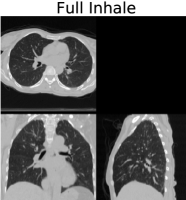

We applied our proposed weighted density registration algorithm to the first subject from the DIR dataset. This subject has images at 10 timepoints and has a set of 300 corresponding landmarks between the full inhale image and the full exhale image. These landmarks were manually chosen by three independent observers. Without any deformation, the landmark error is 4.01 mm (SD 2.91 mm). Using our method, the landmark error is reduced to 0.88 mm (SD 0.94 mm), which is only slightly higher than the observer repeat registration error of 0.85 mm (SD 1.24 mm).

We implement our algorithm on the GPU and plot the energy as well as the Fisher-Rao metric with and without applying the deformation. These results are shown in Figure 6. In this figure, we show that we have excellent data match, while the deformation remains physiologically realistic: inside the lungs there is substantial volume change due to respiration, but the deformation outside the lungs is volume preserving. With a voxel dataset, our algorithm takes approximately nine minutes running for four thousand iterations on a single nVidia Titan Z GPU.